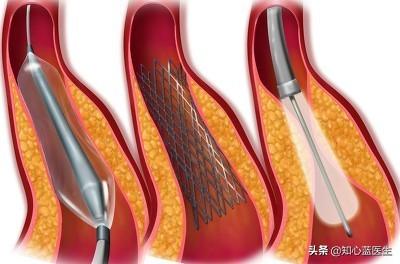

ステップ1、パンク。末梢動脈を見つけ、この動脈から穿刺を行うが、最も一般的な選択は、手の付け根か太ももの末梢動脈を選択することである。

ステップ2、チューブの挿入。その末梢血管開口部からシースを挿入し、適切なサイズのシースを選択してガイドワイヤーを進め、冠動脈開口部付近の心臓までゆっくりと送り込む。

ステップ3:軌道を確立する。最初のガイドワイヤーは冠動脈より太いので、この時は細いガイドワイヤーを選んで冠動脈病変の遠位部を通過させ、まずバルーンで拡張しなければならない。

ステップ4:ステントを留置する。バルーンの拡張が完了したら、このガイドワイヤーに従ってステントを留置する。

これが心臓ステント手術の大まかな流れだ。 経験を積んだ。熟練した医師は、この手術を30分以上かけて行う!そのため、心臓ステント手術を専門とする医師にとっては、そうである。大きな作戦ではない。。